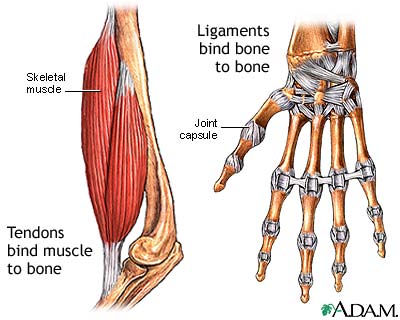

272. MAINTENANCE: Body mechanics slideshow

• 272. MAINTENANCE: Body mechanics slideshow August 26, 2025